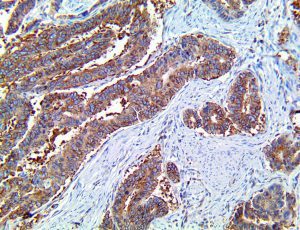

This activation induces inflammatory monocytes to highly express IL-6, starting a localized and then systemic cascade effect that results in hyperproduction of IL-6, which accelerates the inflammatory process. Because IL-6 also increases vascular permeability, excessive levels cause blood vessels to become very leaky. This, along with clotting factors released from vascular endothelial cells, stimulates the coagulation cascade, resulting in microthrombosis (tiny clots), which leads to ischemia and tissue death of the kidney, intestines, heart, liver, brain and extremities.